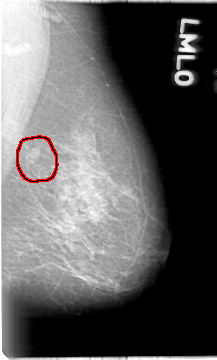

D_4019_1.LEFT_MLO

LEFT_MLO LINES 5386 PIXELS_PER_LINE 3241 BITS_PER_PIXEL 12 RESOLUTION 43.5 OVERLAY

FILE: D_4019_1.LEFT_MLO.OVERLAY

TOTAL_ABNORMALITIES 1

ABNORMALITY 1

LESION_TYPE MASS SHAPE OVAL MARGINS MICROLOBULATED

ASSESSMENT 0

SUBTLETY 4

PATHOLOGY BENIGN

TOTAL_OUTLINES 1

BOUNDARY